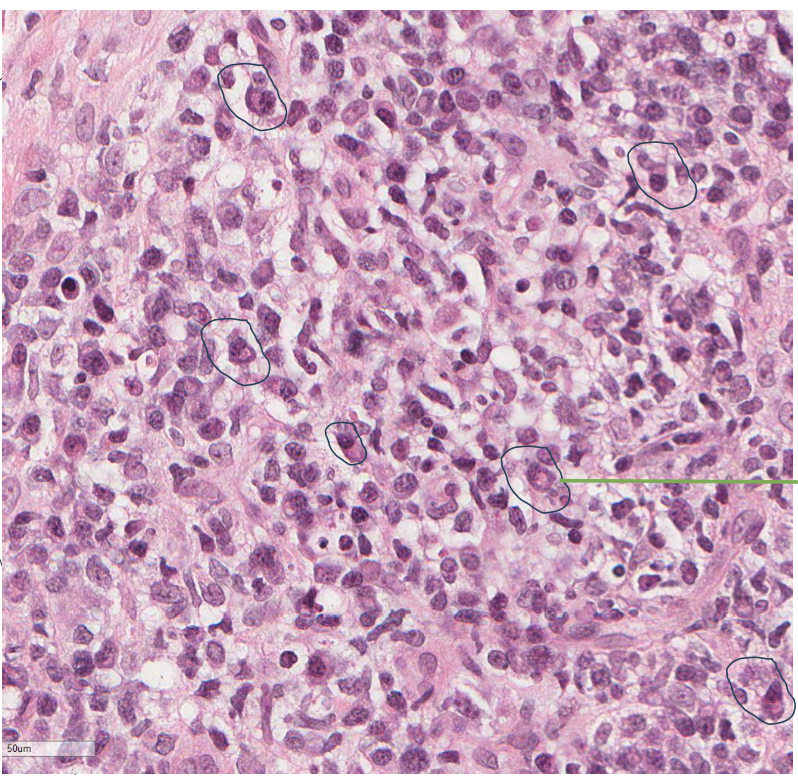

name the biological process shown in this image

acute inflammation

neutrophils !!